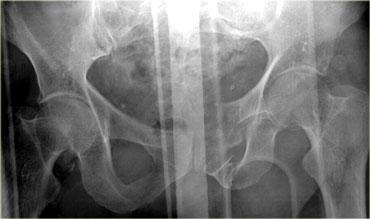

Bên trái là hình ảnh của một nam giới 65 tuổi bị xe ô tô đâm ở tốc độ vừa phải.

Mất ý thức trong 2 phút.

Đặt thông tiểu Foley và phát hiện đái máu đại thể.

Phim X-quang cho thấy gãy xương mu di lệch vừa với các mảnh xương nhọn ở vùng bàng quang.

Bên trái là hình ảnh CT chấn thương thường quy.

Nhận xét các dấu hiệu hình ảnh?

Có hình ảnh gãy xương chậu di lệch với một mảnh xương nhọn hướng về phía bàng quang.

Có dịch trong khoang trước bàng quang (khoang Retzius).

Khi có gãy xương chậu, tỷ lệ vỡ bàng quang là 10%.

Khi có vỡ bàng quang, hầu như luôn luôn kèm theo gãy xương chậu.